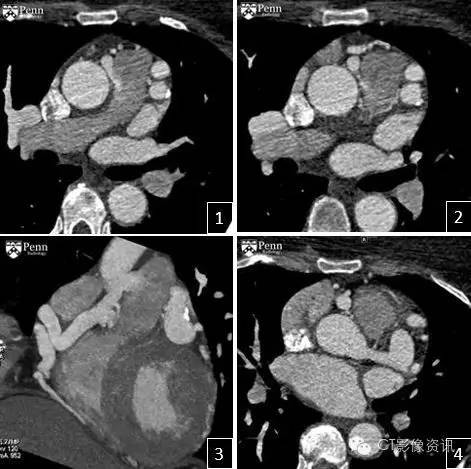

冠状动脉CTA图像如下

表现 回顾性心电门控冠脉CTA,在轴位图像(图1、2)和冠状位最大密度投影图像(图3)均显示了右侧冠状动脉起源于肺动脉主干的异常。左侧冠脉主干显著扩张增粗(图4),因为左侧冠脉的分支对右侧冠状动脉分支建立了侧支循环代偿。右侧冠状动脉没有明显的狭窄与心肌桥存在。左心室肥大,左室射血分数为55%。

影像学征象-冠状动脉CTA 右侧冠状动脉由肺动脉发出。 侧支循环会导致左、右冠状动脉冠的分支扩张。